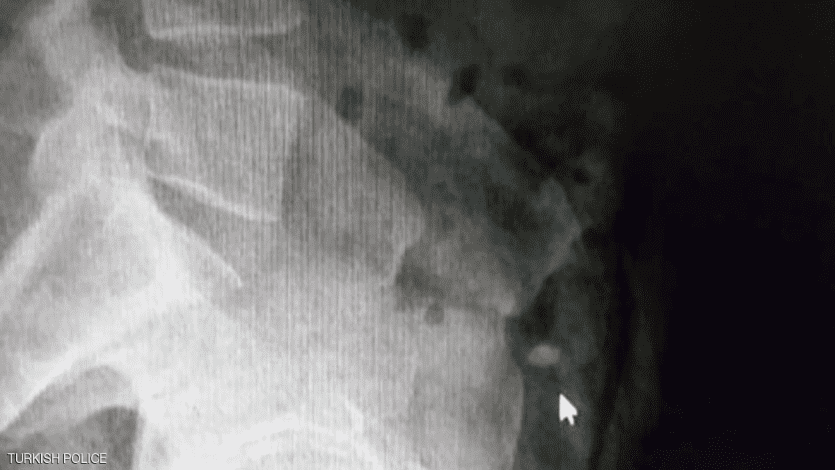

وأمرت الشرطة بنقل السارق إلى المستشفى، من أجل إجراء عملية جراحية للعثور على الخاتم، ما لم يعد الأيرلندي الخاتم بـ"الطريقة الطبيعية".

وقد قفز مرارا في المستشفى لتحريك الخاتم في أحشائه لمدة 36 ساعة، لكن جهوده كانت بلا جدوى، وبعد ذلك لجأت السلطات إلى استخراج الألماس عبر عملية جراحية.